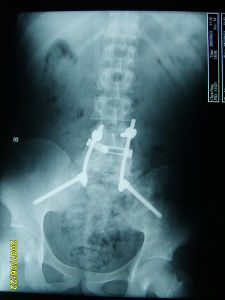

體格檢查除腰骶部有壓痛及叩擊痛外,一般無陽性體徵。血沉及抗“0”均為正常。X線檢查亦無異常發現,有時可有腰骶椎的退行性改變。